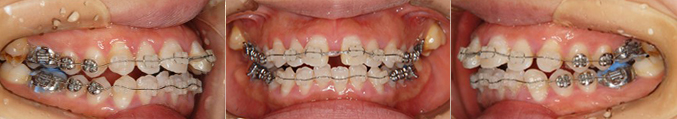

症例:上下の前歯にガタガタのある症例(女性 14歳11ヶ月)

症状:前歯部の叢生(前歯のガタガタ)、八重歯

治療期間:マルチブラケット装置を2年6ヶ月使用

治療費:契約料60万円(セラミックブラケット)+毎回の調節料(税別)

副作用とリスク:

- 歯を移動すると幾分か歯根が吸収されて短くなることがあります。

- 特に生活に支障がない場合が殆どです。歯肉退縮が生じることもあります。

- 歯根吸収および歯肉退縮は共に初診時で認めると進行するリスクが高まる傾向です。

- また前歯のガタガタが著しい方の場合、歯を配列した後に歯間部の骨量が足りず空隙が生じる場合があります。成人の方の方が生じやすいです。

上下の前歯のガタガタに加えて、咬み合わせが深い状態です。上下のガタガタの量が著しく多いため、上下顎両側の第一小臼歯の抜歯を行った上で歯を配列しています。

その後、マルチブラケット装置を装着し歯を配列すると…

治療後 17歳5ヶ月

上下の前歯のガタガタと深い咬み合わせが改善され良好な咬み合わせが得られました。スマイルも美しくなりました。